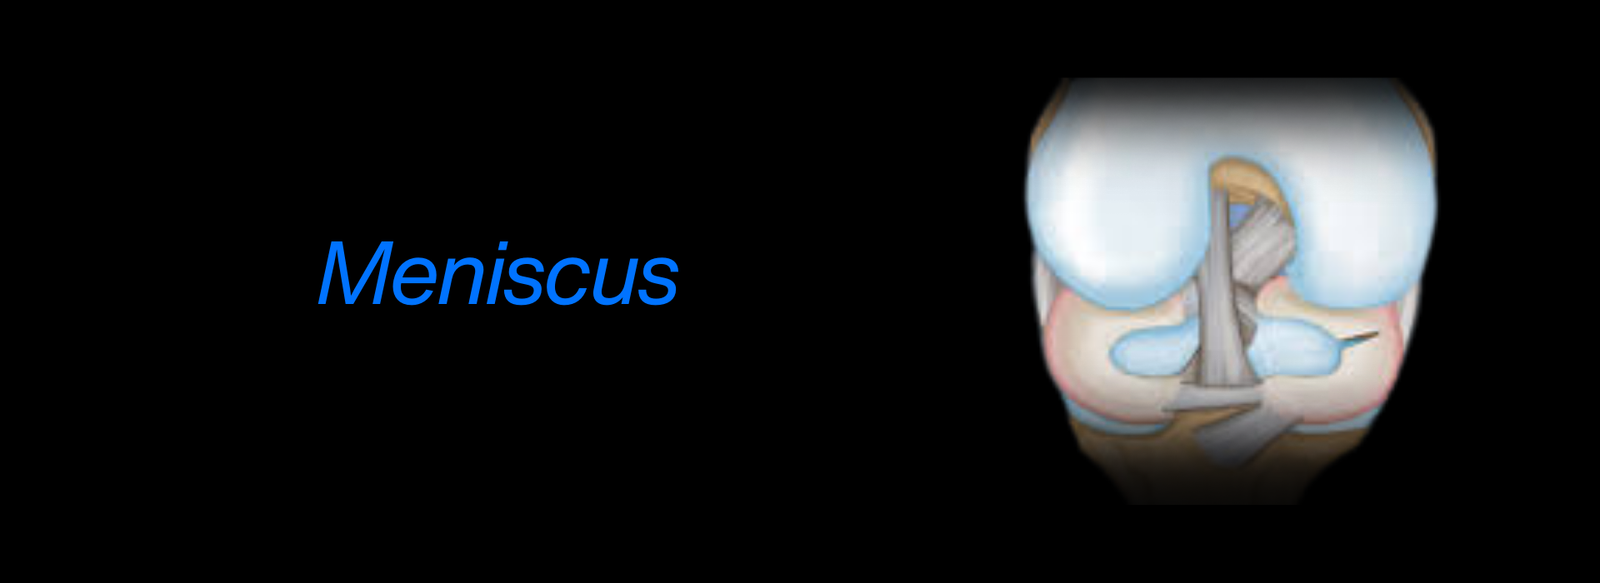

Fellowship in Arthroscopy: Expertise in minimally invasive surgery to diagnose and treat joint conditions, such as torn cartilage or ligament injuries, particularly of the knee, shoulder, and hip.